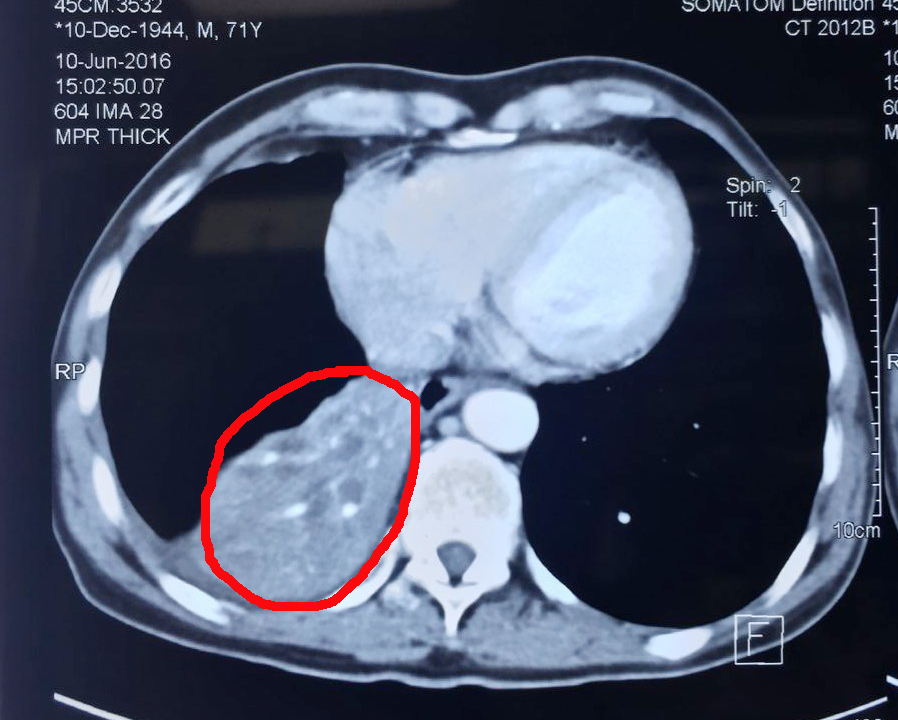

肿瘤治疗前

命途无常,无惊无险经历了大半辈子,杨清贵夫妇正忙着颐养天年,生活却被种下了一颗巨大“炸弹”。2015年,杨清贵持续出现咳嗽、咳痰、呼吸困难10个月,吃药也不见效果。后经检查发现,杨清贵的右肺有一个约10*6cm大小的肿块,确诊为肺癌。杨清贵十分害怕,担心自己能否好起来。“在印尼,癌症是很可怕的,人们都觉得它是绝症。”张英友解释道。医生建议杨清贵手术治疗。杨清贵怕痛,拒绝了。一个星期后,杨清贵的儿媳从网上了解到圣丹福·广州现代(肿瘤)医院,她建议杨清贵:“爸,你到中国去吧,那里的广州现代(肿瘤)医院不用开刀。”到雅加达办事处预约好入院时间,一周后,杨清贵来到了圣丹福·广州现代(肿瘤)医院。